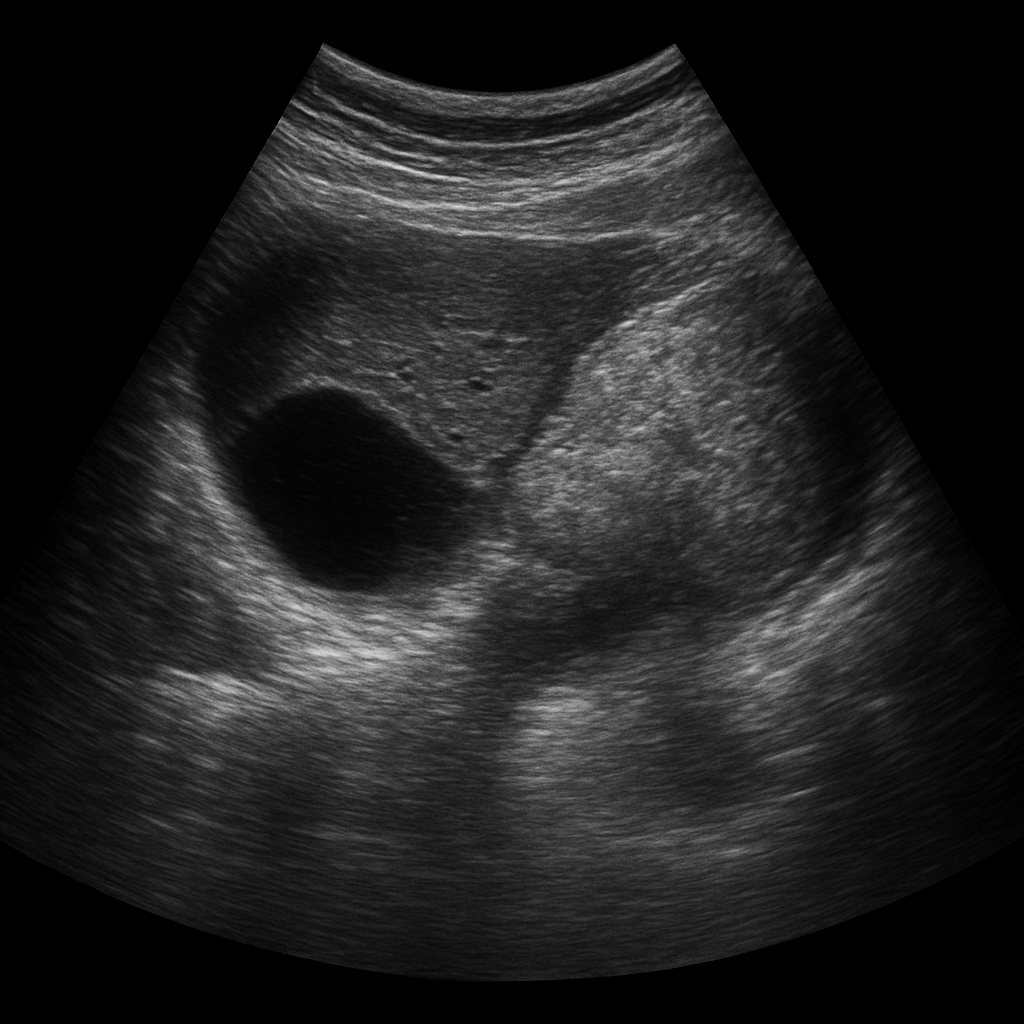

L’échographie abdominale repose sur l’émission d’ondes ultrasonores à haute fréquence à travers une sonde, appliquée sur la peau. Ces ondes se propagent à travers les tissus et sont réfléchies différemment selon la nature des structures qu’elles rencontrent (liquide, tissu dense, gaz, os). Le signal de retour est interprété par un logiciel informatique qui crée des images en temps réel.

Le radiologue, ou le médecin échographiste, peut ainsi observer l’aspect des organes, rechercher des anomalies morphologiques, mesurer des structures et, dans certains cas, guider des gestes diagnostiques ou thérapeutiques.

3. Les reins et voies urinaires hautes

Les reins peuvent être explorés à la recherche de calculs rénaux, de kystes, de tumeurs, ou encore d’une dilatation des cavités rénales (hydronéphrose). On peut aussi y dépister une malformation congénitale ou une infection (comme une pyélonéphrite), bien que le diagnostic repose avant tout sur la clinique et le scanner.

4. Le pancréas

Le pancréas est parfois difficile à visualiser, surtout en raison des gaz intestinaux ou d'obésité. L’échographie permet d’observer sa taille, sa forme et de rechercher des signes indirects de pancréatite aiguë ou chronique, des masses ou des kystes.